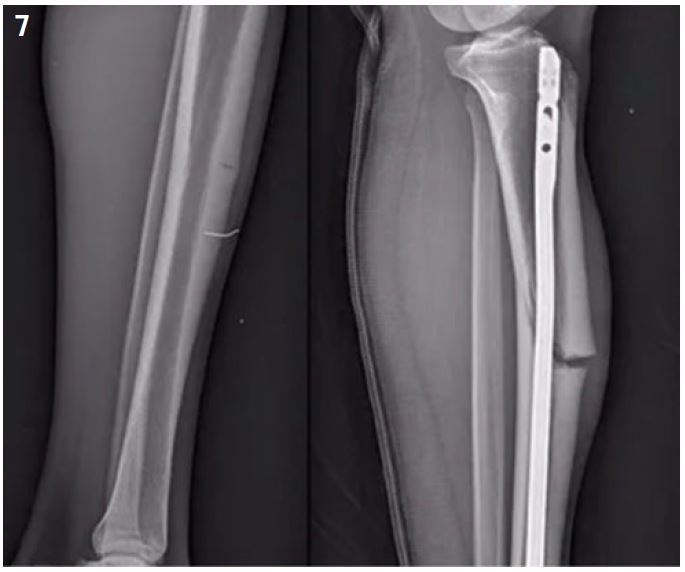

Considering the high rate of non-union, surgical management is widely recommended. It may be a simple compression plate on the convexity of the tibial at the level of the fracture site. For others, the placement of a centro-medullary nail will be necessary7,15,28 (Figures 6 and 7).

Figure 6: Mid shaft tibial stress fracture: osteosynthesis by plate.

Figure 7: Mid shaft tibial stress fracture: osteosynthesis by intramedullary nailling.